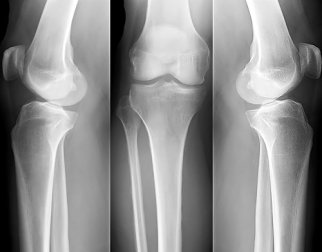

Dicas para combater a osteoporose

A melhor maneira de combater a osteoporose é fortalecendo os ossos, não importando a sua idade.